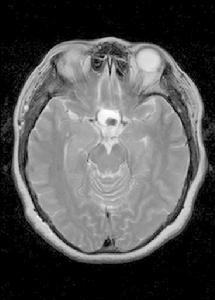

為先天性腫瘤,約占顱內腫瘤的5%。多見於兒童及少年,男性多於女性。腫瘤大多位於鞍上區,可向第三腦室、下丘腦、腳間池、鞍旁、兩側顳葉、額葉底及鞍內等方向發展,壓迫視神經及視交叉,阻塞腦脊液循環而導致腦積水。症狀體徵主要表現有視力障礙、視野缺損、尿崩、肥胖、發育延遲等。成年男性有性功能障礙,女性有月經不調。晚期可有顱內壓增高。

為先天性腫瘤,多見於兒童及少年,男性多於女性。腫瘤大多位於鞍上區,可向第三腦室、下丘腦、腳間池、鞍旁、兩側顳葉、額葉底及鞍內等方向發展,壓迫視神經及視交叉,阻塞腦脊液循環而導致腦積水。

腫瘤大多位於鞍上區,可向第三腦室、下丘腦、腳間池、鞍旁、兩側顳葉、額葉底及鞍內等方向發展,壓迫視神經及視交叉,阻塞腦脊液循環而導致腦積水。腫瘤大多為囊性,囊液呈黃褐色或深褐色,內含大量膽固醇晶體。瘤壁上有鈣化斑塊。顯微鏡下示瘤細胞主要由鱗狀或柱狀上皮細胞組成,有的排列成牙釉質器官樣結構。 [編輯本段]診斷檢查顱骨X線攝片除見蝶鞍增大變淺外,可見鞍上區有鈣化。